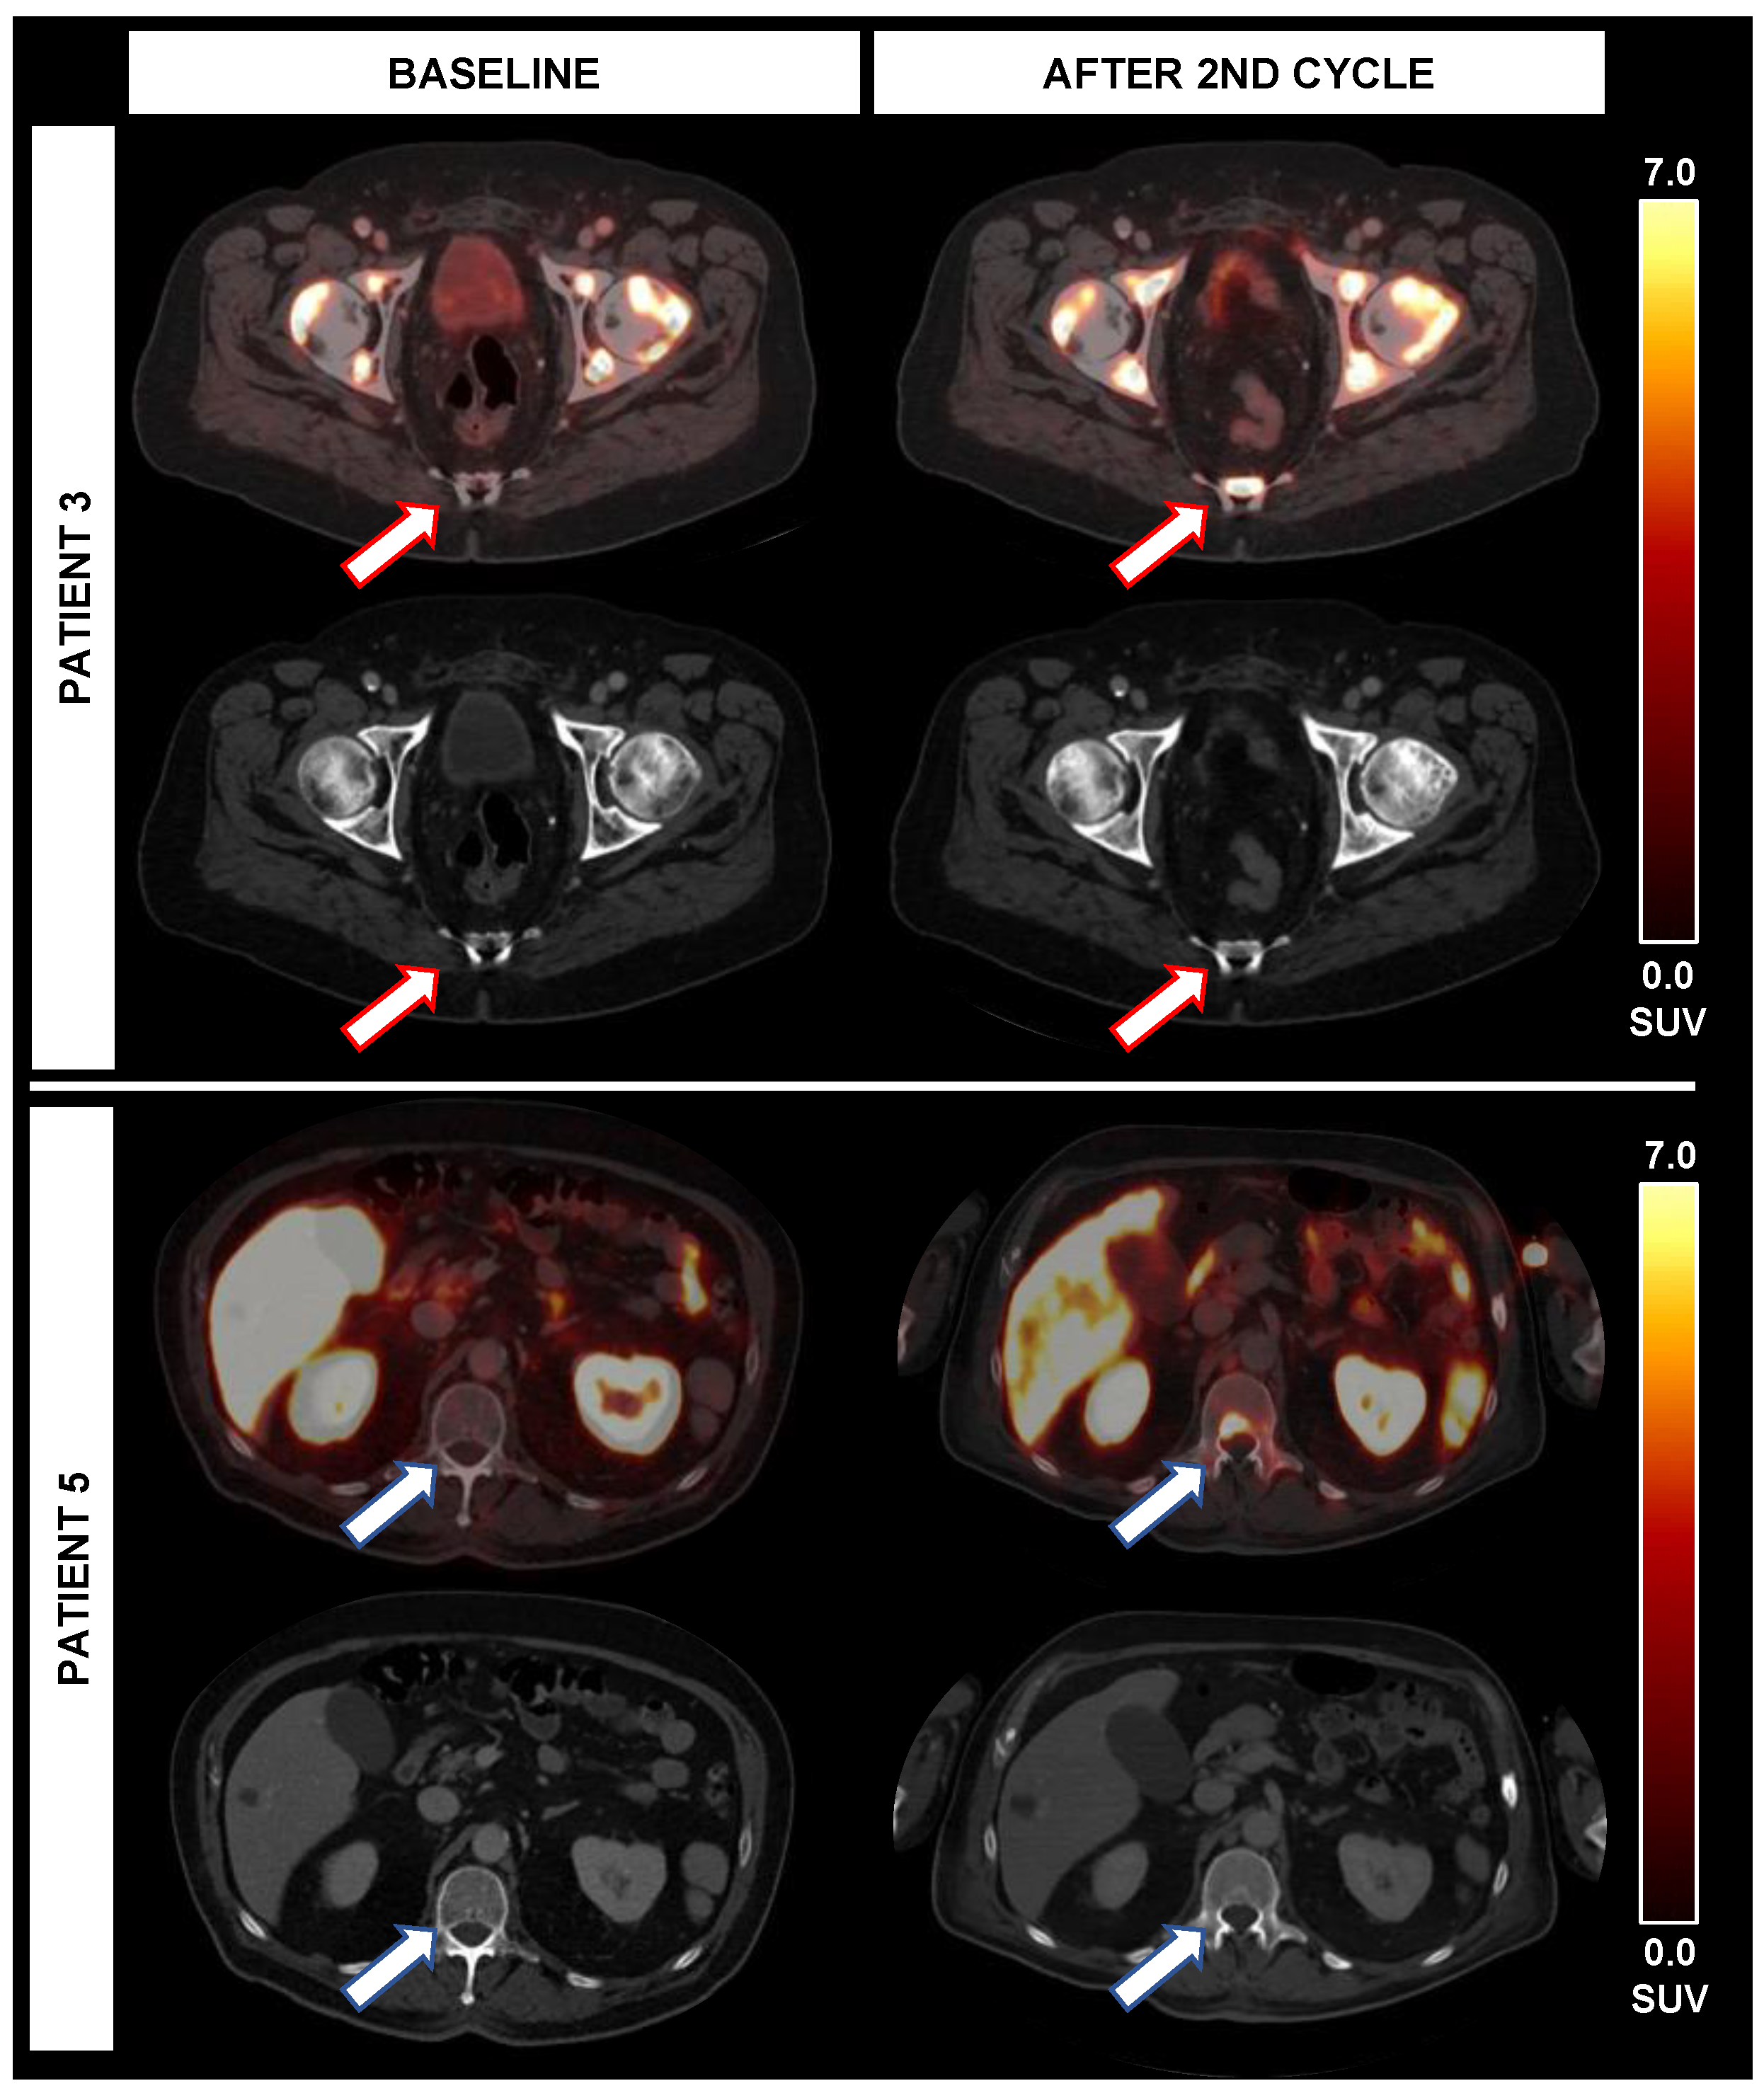

| Patient | Response TTV | Δ% TTV | Response SUVmean | Δ% SUVmean | Response SUVmax | Δ% SUVmax | Response mPERCIST | Δ% mPERCIST | Response RECIST | Δ% RECIST | Response RECIST | Δ% PSA | Δ% LDH | Δ% AP | OS [mo] |

|---|---|---|---|---|---|---|---|---|---|---|---|---|---|---|---|

| 1 | PR | −39.3% | PR | −37.5% | PR | −54.9% | PR | −36.8% | SD | +2.6% | SD | −14.2% | −3.5% | −30.6% | 10 |

| 2 | PR | −67.9% | SD | −24.1% | PR | −46.0% | PR | −65.3% | SD | −13.9% | SD | −67.3% | +16.0% | −10.3% | 26 |

| 3 | SD | +2.6% | SD | −21.6% | PR | −81.6% | PD * | n.e. | Non-CR/Non-PD | n.a. | Non-CR/Non-PD | −32.8% | −11.6% | +165.3% | 18 |

| 4 | PR | −62.4% | SD | −24.1% | PD | +33.6% | PR | −60.5% | Non-CR/Non-PD | n.a. | Non-CR/Non-PD | −41.4% | −23.8% | +42.9% | 11 ° |

| 5 | PR | −64.5% | SD | −8.1% | PD | +74.2% | PD * | n.e. | PD | n.e. | PD | −25.2% | +126.6% | +20.5% | 5 |

| 6 | PR | −97.8% | SD | −23.3% | PR | −62.2% | PR | −66.4% | SD | +8.9% | SD | −20.8% | −29.6% | +55.8% | 11 |

| 7 | PR | −59.6% | PR | −42.3% | PR | −45.2% | PR | −78.5% | Non-CR/Non-PD | n.a. | Non-CR/Non-PD | −44.4% | +22.0% | −9.2% | 20 |